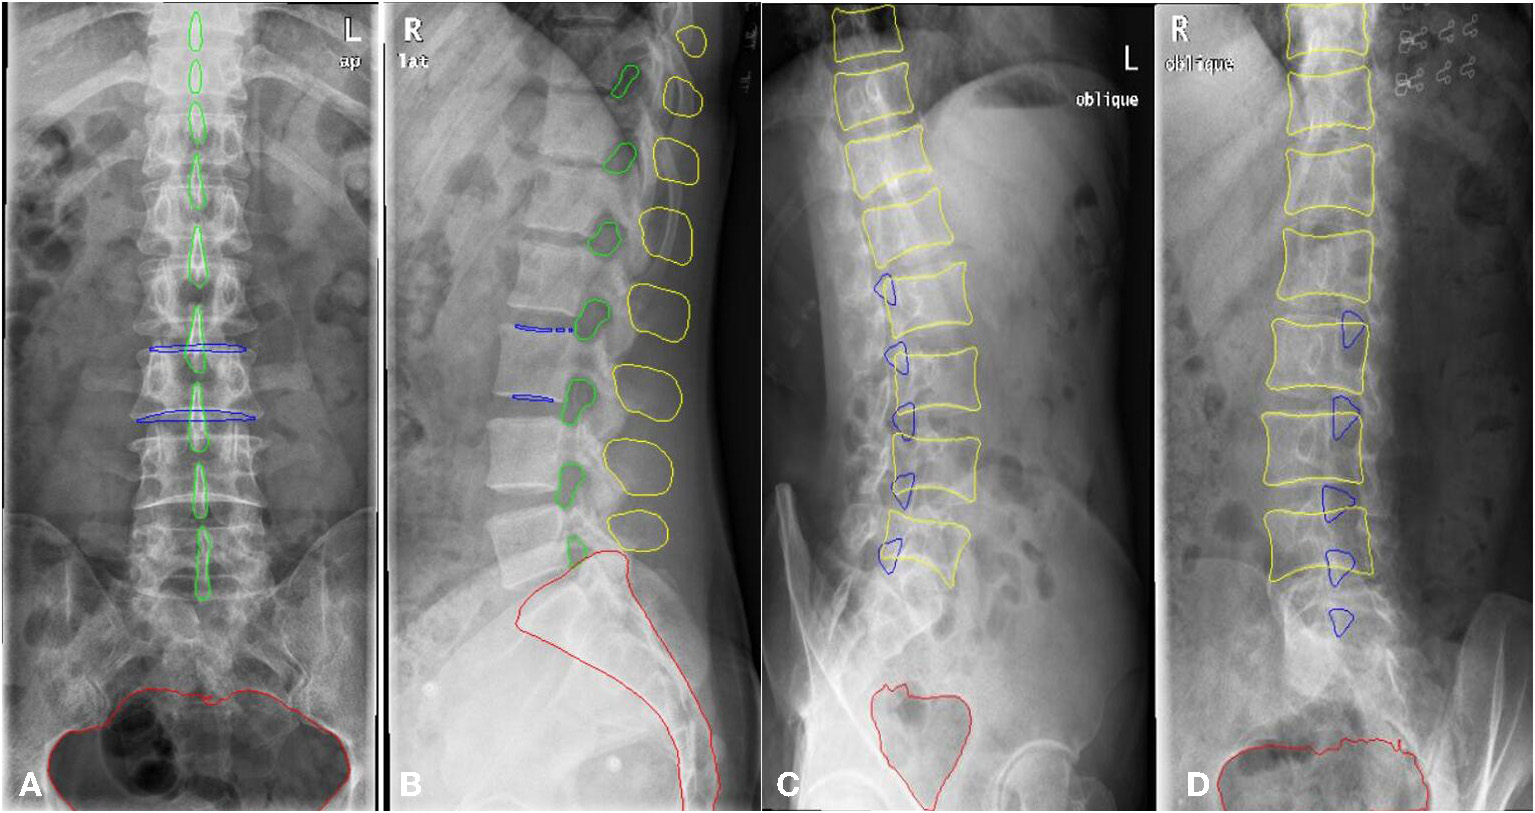

A total of 1,389 patients were recruited into this cohort study by the First Affiliated Hospital of Wenzhou Medical University (Wenzhou, Zhejiang Province). Each patient had anteroposterior, lateral, and/or oblique position lumbar spine x-ray images taken. The dataset was randomly split into a training and a validation set. The training set consisted of 1,070 patients (800,798, and 623 images for the anteroposterior, lateral, and oblique position, respectively) and the validation set included 319 patients (200, 205, and 156 images for the anteroposterior, lateral, and oblique position, respectively). The regions of the lumbar vertebrae, pelvis, spinous processes, L3 (the third lumbar vertebra), and bilateral shadow of L3 were labeled on the fontal view of the lumbar spine, as shown in Figure 3A1. The area of the lumbar vertebrae, spinous processes, intervertebral foramen, L3, bilateral shadow of L3, and sacral vertebrae were marked on the lateral view of the lumbar spine, as shown in Figure 3A2. The lumbar vertebrae, inferior articular processes, and pelvis were marked on the oblique view of the lumbar spine, as shown in Figure 3A3. As ground truth for evaluation of the AI segmentation, all x-ray images were first delineated by two experienced radiologists, and then confirmed by a senior radiologist. This retrospective study was performed in accordance with the principles of the Helsinki Declaration and was approved by the institutional ethics committee. Given that this was a retrospective study, the need for obtaining written informed consent from the patients was waived.

Figure 3

The example of manual segmentation and AI segmentation for three positions, anteroposterior (A1,B1), lateral (A2,B2) and oblique view (A3,B3). (A1,A2,A3) Ground truth of segmentation by manual marking. (B1,B2,B3) AI segmentation results.

The scSE U-net model was trained with 1,070 patients (800, 798, and 623 images for the anteroposterior, lateral, and oblique position, respectively) and then tested with the validation set (comprising 319 patients: 200, 205, and 156 images for the anteroposterior, lateral, and oblique position, respectively). The DSC was used to evaluate the segmentation performance. Figure 3 provides an example of manual segmentation and AI segmentation for the three positions.

All segmentation results were then used for the assessment of the qualification of x-ray images according to criteria defined in the textbooks (8, 10), as shown in Table 1. The performance of segmentation algorithms is crucial for x-ray image quality control. For anteroposterior position x-ray images, the outer contour, internal contour, pelvis, and spinous process were segmented by the U-net model. For lateral position x-ray images, segmentations included the outer contour, internal contour, intervertebral foramen, spinous process, and sacral vertebrae. For oblique position images, the inferior articular, vertebra, and pelvis were segmented from the x-ray images.